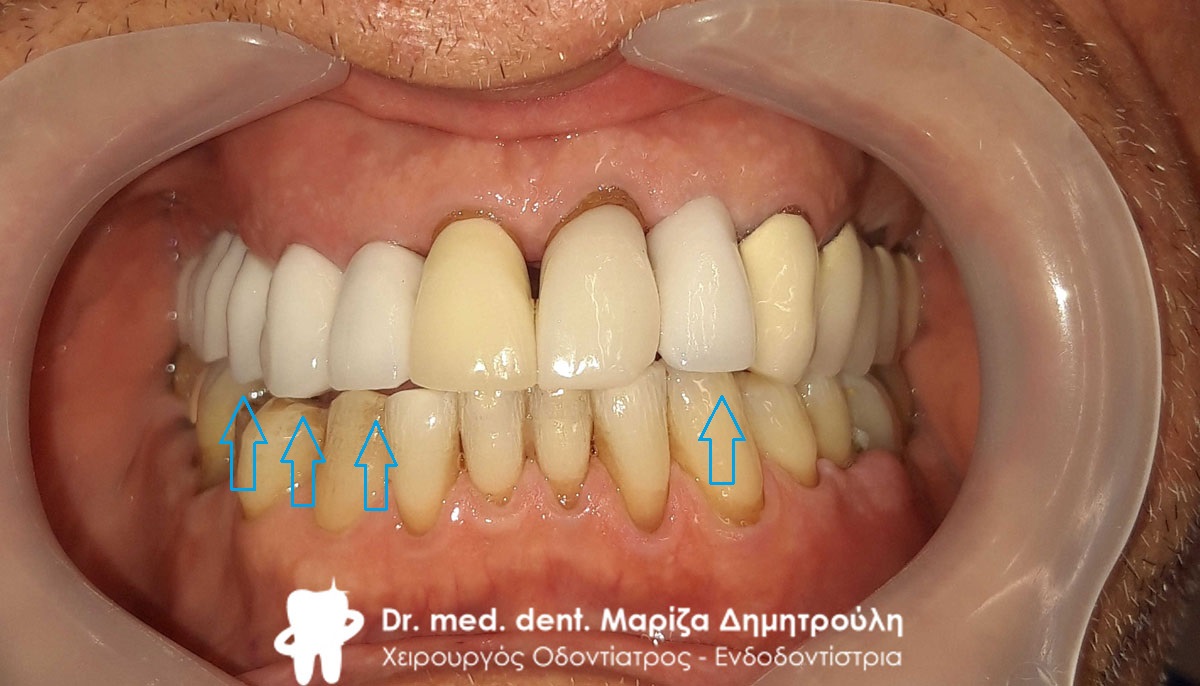

Περιστατικό – Ολική αποκατάσταση της άνω και κάτω γνάθου

Ο ασθενής πήρε την απόφαση μετά από πολλά χρόνια να αποκαταστήσει τα δόντια τόσο της άνω γνάθου όσο και τα δόντια της κάτω γνάθου. Χρειάστηκαν αρκετές συνεδρίες ώστε να ολοκληρωθούν οι απαραίτητες απονευρώσεις και ανασυστάσεις δοντιών. Στη συνέχεια και εφόσον ήταν έτοιμη η προσθετική δουλειά από τον οδοντοτεχνίτη κολλήθηκαν τα ολοκεραμικά πέταλλα στο στόμα του ασθενή.

Αρχική κλινική εικόνα του στόματος του ασθενή

Τελική κλινική εικόνα του στόματος του ασθενή